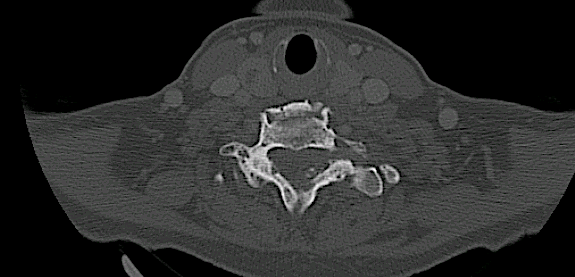

A los dos años consultó nuevamente por presentar clínica de dolor cervical irradiado a MMSS. Tras descartar recidiva, se decidió intervenir la estenosis de canal vía anterior.

Rx 6 meses

Rm 6 meses